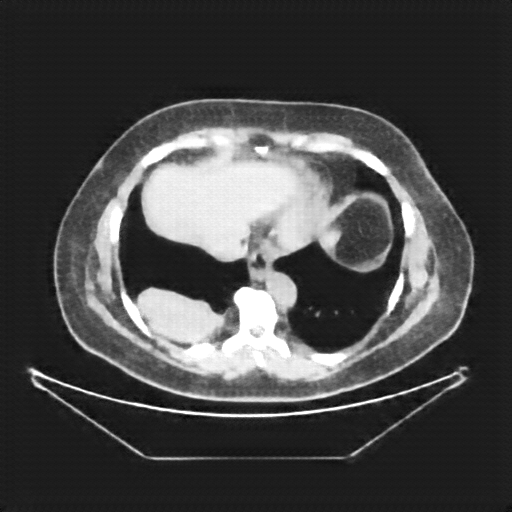

Generated VENOUS CT scan (A→B translation)

Full window (WL 1023.5, WW 4095 β†’ Low βˆ’1024, High +3071)

Lung window (WL -600, WW 1500 β†’ Low βˆ’1350, High +150)

Mediastinum window (WL 40, WW 400 β†’ Low βˆ’160, High +240)